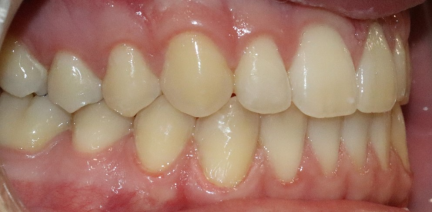

Distalisation, courbe de Spee nivelée, égression, expansion, rétraction, réduction interproximale, traitement de phase III, élastiques : Classe III

- Nous avons planifié une distalisation séquentielle de l'arcade inférieure pour corriger la molaire et la canine de classe III en molaire et canine de classe I.

- La distalisation séquentielle de l'arcade inférieure a fourni l'espace nécessaire pour rétracter les dents antérieures inférieures et donc corriger l'occlusion croisée des dents latérales supérieures.

- Le surplomb antérieur créé nous a permis de rétracter les incisives supérieures et donc de corriger la biprotusion dentaire.

- La collaboration des patients pendant la durée totale du traitement était excellente avec le port d'aligners à temps plein (22 heures/jour) et d'élastiques de classe III.

État final